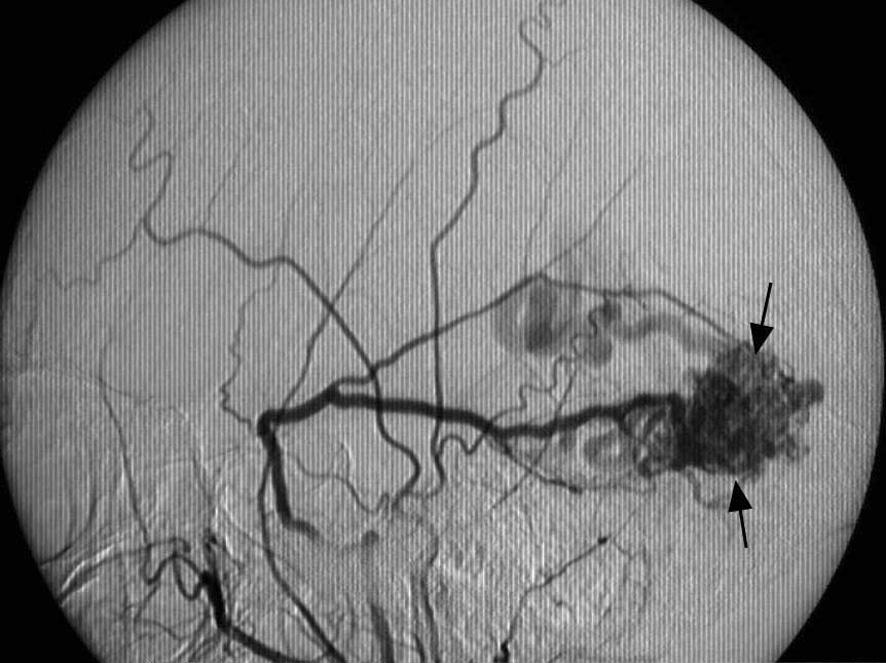

Artère méningée moyenne, vue latérale gauche. a. Dissection. (1 : Branche frontale. 2 : Branche pariétale.) b. Artériographie (flèche).

P athologie

Les fistules artérioveineuses durales intracrâniennes (fig. 1.15) sont des communications directes anormales entre les artères méningées et les veines ou sinus duraux. Lorsque la fistule se draine par des veines corticales, elle peut se rompre et provoquer une hémorragie cérébrale.

Fistule artérioveineuse durale (flèches) pariéto-occipitale à drainage veineux cortical. Angiographie carotidienne externe gauche, profil.